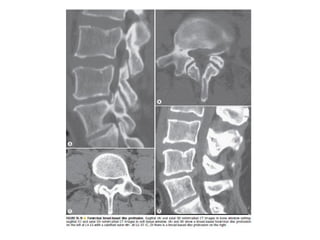

The spine is made up of vertebrae separated by intervertebral discs that allow movement and provide shock absorption. Diagnostic imaging plays an important role in evaluating the spine for conditions like fractures, disc herniations, spinal stenosis, and tumors. Imaging modalities like X-rays, CT scans, MRI, and bone scans can detect abnormalities and aid physicians in diagnosing and treating various spinal disorders.